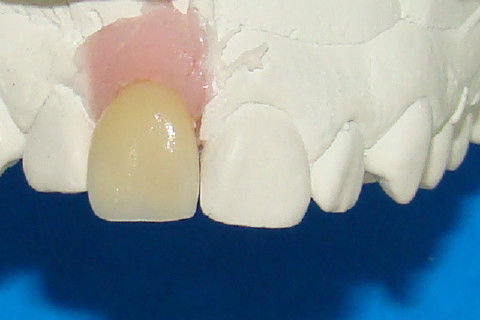

Coping para coroa metalo-ceramica no modelo

Vista palatine do coping

Aspecto vestibular da coroa metalo-cerâmica no modelo

Aspecto palatino da coroa metalo-cerâmica no modelo